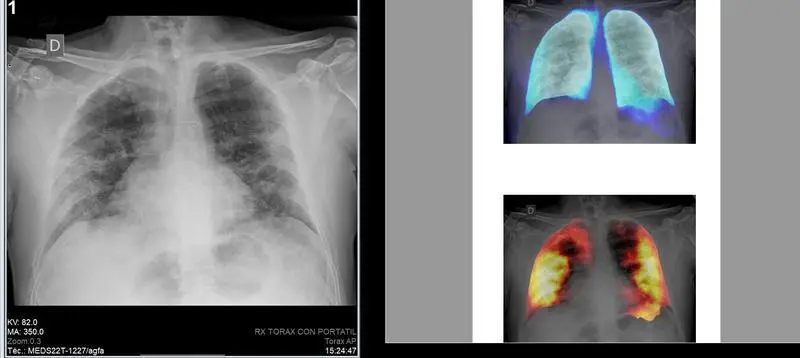

En 2020 se realizaron en España alrededor de 43 millones de pruebas de diagnóstico por imagen, con un valor global de 2.700 millones de euros, según el Observatorio Sectorial DBK de Informa, filial de Cesce.

El observatorio estima que el número de pruebas fue un 15,5% inferior al contabilizado en 2019, debido al impacto de la pandemia de la Covid-19 en la actividad de los centros de diagnóstico por imagen, que supuso la paralización de gran parte de las pruebas en la primera mitad del año y la posterior limitación de afluencia debido a los protocolos de seguridad.